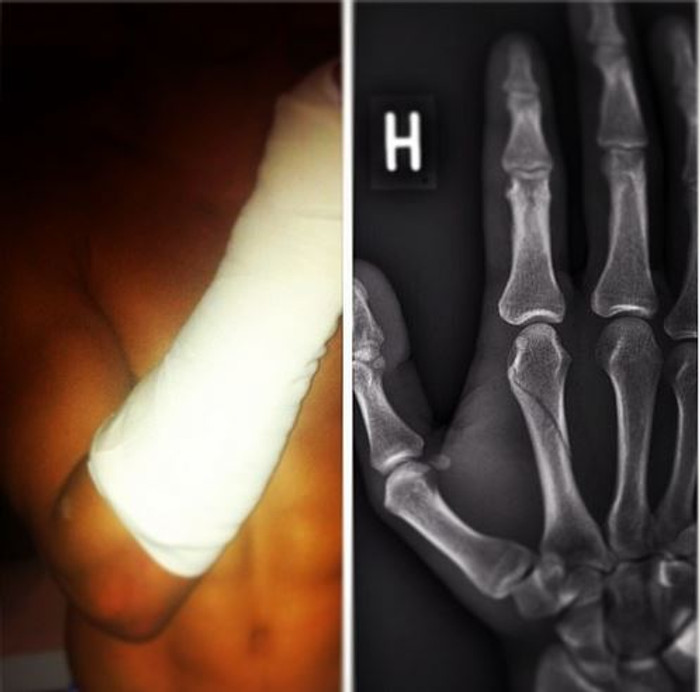

Rúrik Gíslason, leikmaður FC Kaupmannahafnar, handarbrotnaði í 1-1 jafntefli liðsins gegn Vestsjælland í dönsku úrvalsdeildinni í gærkvöldi.

,,Það var brotið á mér og ég datt illa á hendina. Þetta er pirrandi en það er betra að þetta sé hendin en fóturinn," sagði Rúrik við Fótbolta.net í dag.

Rúrik reiknar ekki með að missa af neinum leikjum þrátt fyrir meiðslin.